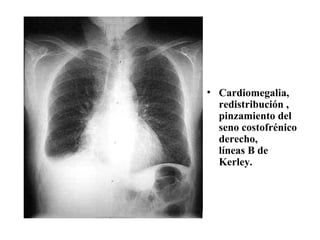

a.  Hallazgos radiológicos  El hallazgo más temprano es la llamada  redistribución : la  dilatación  de los  vasos  de las  zonas altas  del pulmón con vasos normales en las zonas basales. Los hallazgos radiológicos incluyen en primer lugar la  presencia  de las líneas septales de  Kerley A y B      engrosamiento septos interlobulillares .

Kerley B:  horizontales , rectas,  4 mm  de anchas y  1-3 cm  de largas. Se ven en los  senos costodiafragmáticos , visibles en la  parte anterior  de los pulmones. Kerley A: líneas  densas , rectas o ligeramente anguladas,  4-5 cm  de longitud, que pueden verse en  cualquier zona , tienen tendencia a dirigirse  hacia el hilio , visibles en el  espacio retroesternal .

Hipertensión venosa pulmonar moderada, debida a obstrucción de AI. Redistribución pulmonar y edema con líneas de Kerley B. Sombras vasculares engrosadas en lob sup y adelgazadas en lob inf. Cardiomegalia con crecimiento de VD y aretria pulmonar prominente.

Cardiomegalia, redistribución , pinzamiento del seno costofrénico derecho, líneas B de Kerley.